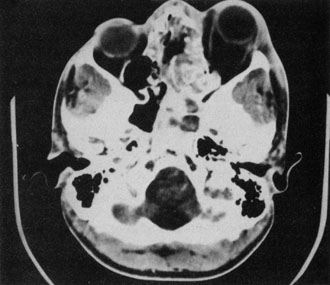

Rhinocerebral mucormycosis originates as a rhinitis, parapharyngitis, or sinusitis, and spreads by invasion of blood vessel walls, causing a necrotizing vasculitis with thrombosis of the vascular lumina and resultant infarction. The patient typically presents with unilateral orbital apex syndrome, including severe pain, visual loss, total ophthalmoplegia, corneal anesthesia, and multiple cranial nerve palsies.127 Orbital cellulitis presenting with early visual loss is one of the hallmarks of mucormycosis.72 Gangrene may occur of external periorbital tissues as well as of the hard palate and nose, and eschar-like crusting may be observed within the nose or on the hard palate (Fig. 23). Obstruction of the central retinal artery, ciliary arteries, and choroidal circulation can also be seen.124,125 Brain damage may occur because of spread of infection or infarction or occlusion of affected intracranial vessels.72

Fig. 23. Mucormycosis of the right ethmoidal sinus, with right orbital subperiosteal abscess formation. A. T1-weighted axial image. B. T2-weighted image. Note brain abscess.

CT shows sinusitis with or without bone destruction and is indistinguishable from other causes of orbital cellulitis.128 MRI may show carotid narrowing, occlusion, and absent flow in the superior ophthalmic vein (Fig. 24).72

Diagnosis is made by having a large index of suspicion and obtaining specimens of nasal turbinate, sinus, or infected orbital tissue. Large, branching nonseptate hyphae are readily apparent on hematoxylin and eosin staining or with methenamine silver staining (see Fig. 23). These hyphae can be grown on fungal culture.